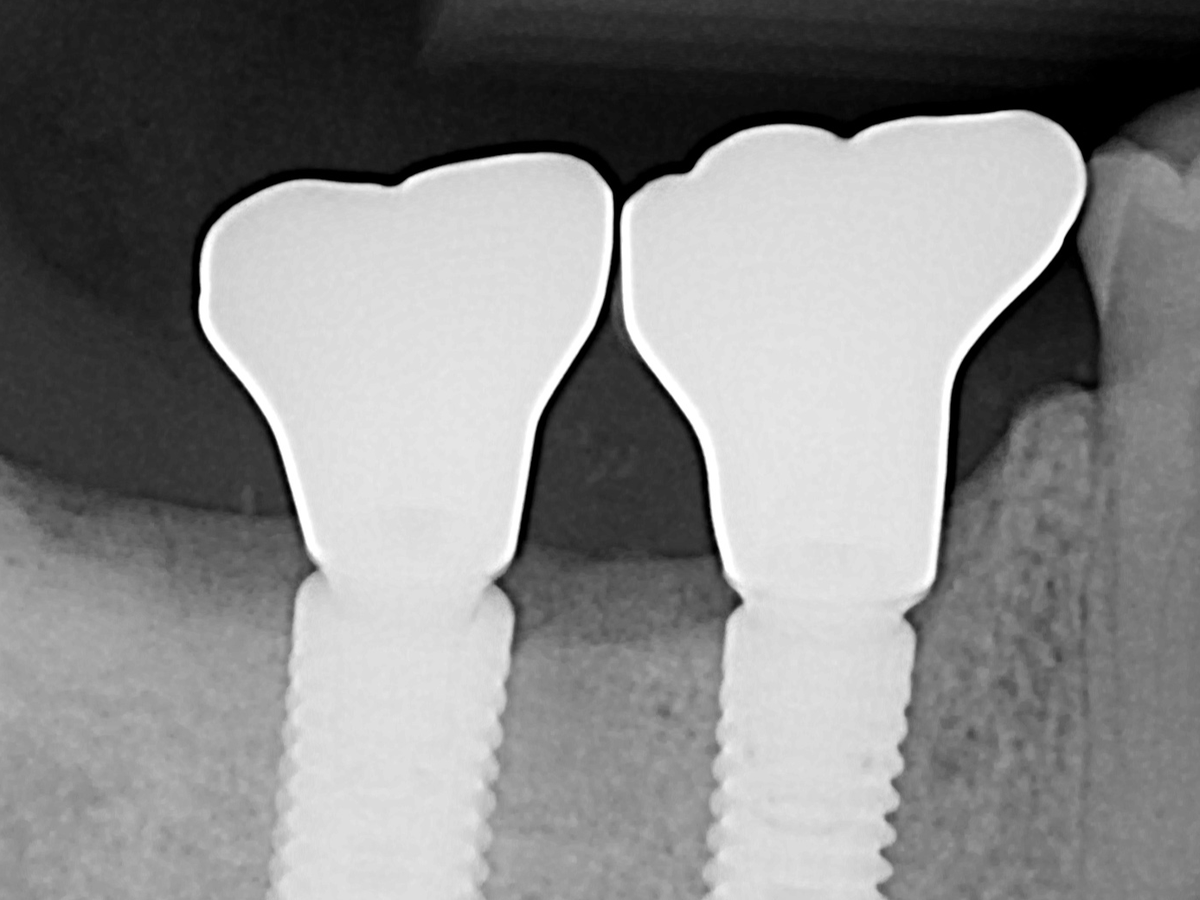

Two dental implants I got five years ago that enable me to chew on the right side of my mouth failed this year. In June 2025, I was billed $2,721 for replacement of the abutment (screw) and crown on one implant. In September 2025, I was billed an additional $1,656 for removal of the other implant and for a bone graft due to a gum infection that impacted the foundation of this other implant.